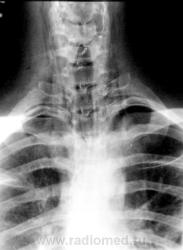

Молодой человек получил удар в шею. Был доставлен в травмпункт, дан барий для исключения перфорации пищевода.

Перфорации похоже нет, но есть другое...

Это чем же его ударили? Я так понимаю, ограниченный пневмоторакс слева  + эмфизема мягких тканей шеи?

Шейный кифоз настораживает.Отсутствие легочного рисунка в верхней доле левого легкого с краем легкогоЭмфизема мягких тканей шеи..Согласна с коллегой.Пару лет назад по кифозу ШОП, увеличению превертебрального пространства и столбу воздуха поставили разрыв пищевода.Дали  контраст-подтвердили.

Затекания контраста за пределы пищевода на представленных рентгенограммах не выявлено. Нет фазы тугого заполнения. Левосторонний пневмоторакс.

Да, ЛОРа 100% надо на консультацию, т.к. барий затек не туда.